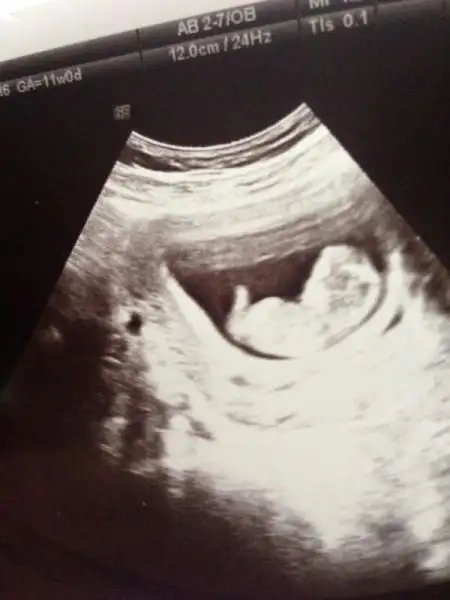

ya kızlar benim iki hafata önceki ultrasonum var belli midir? dr erkek muhtemelen dedi ama kesin demedi. yeni ultrasonu ekleyemedim bir türlü ışık patlaması oluyor. çocuğun kafası kocaman görüyodu korktum ya siiznkilerde de öyle oldu mu? kötü bişey olsa dr söylerdi dimi? ya da ultrasn eski diye mi öyle çıktı?